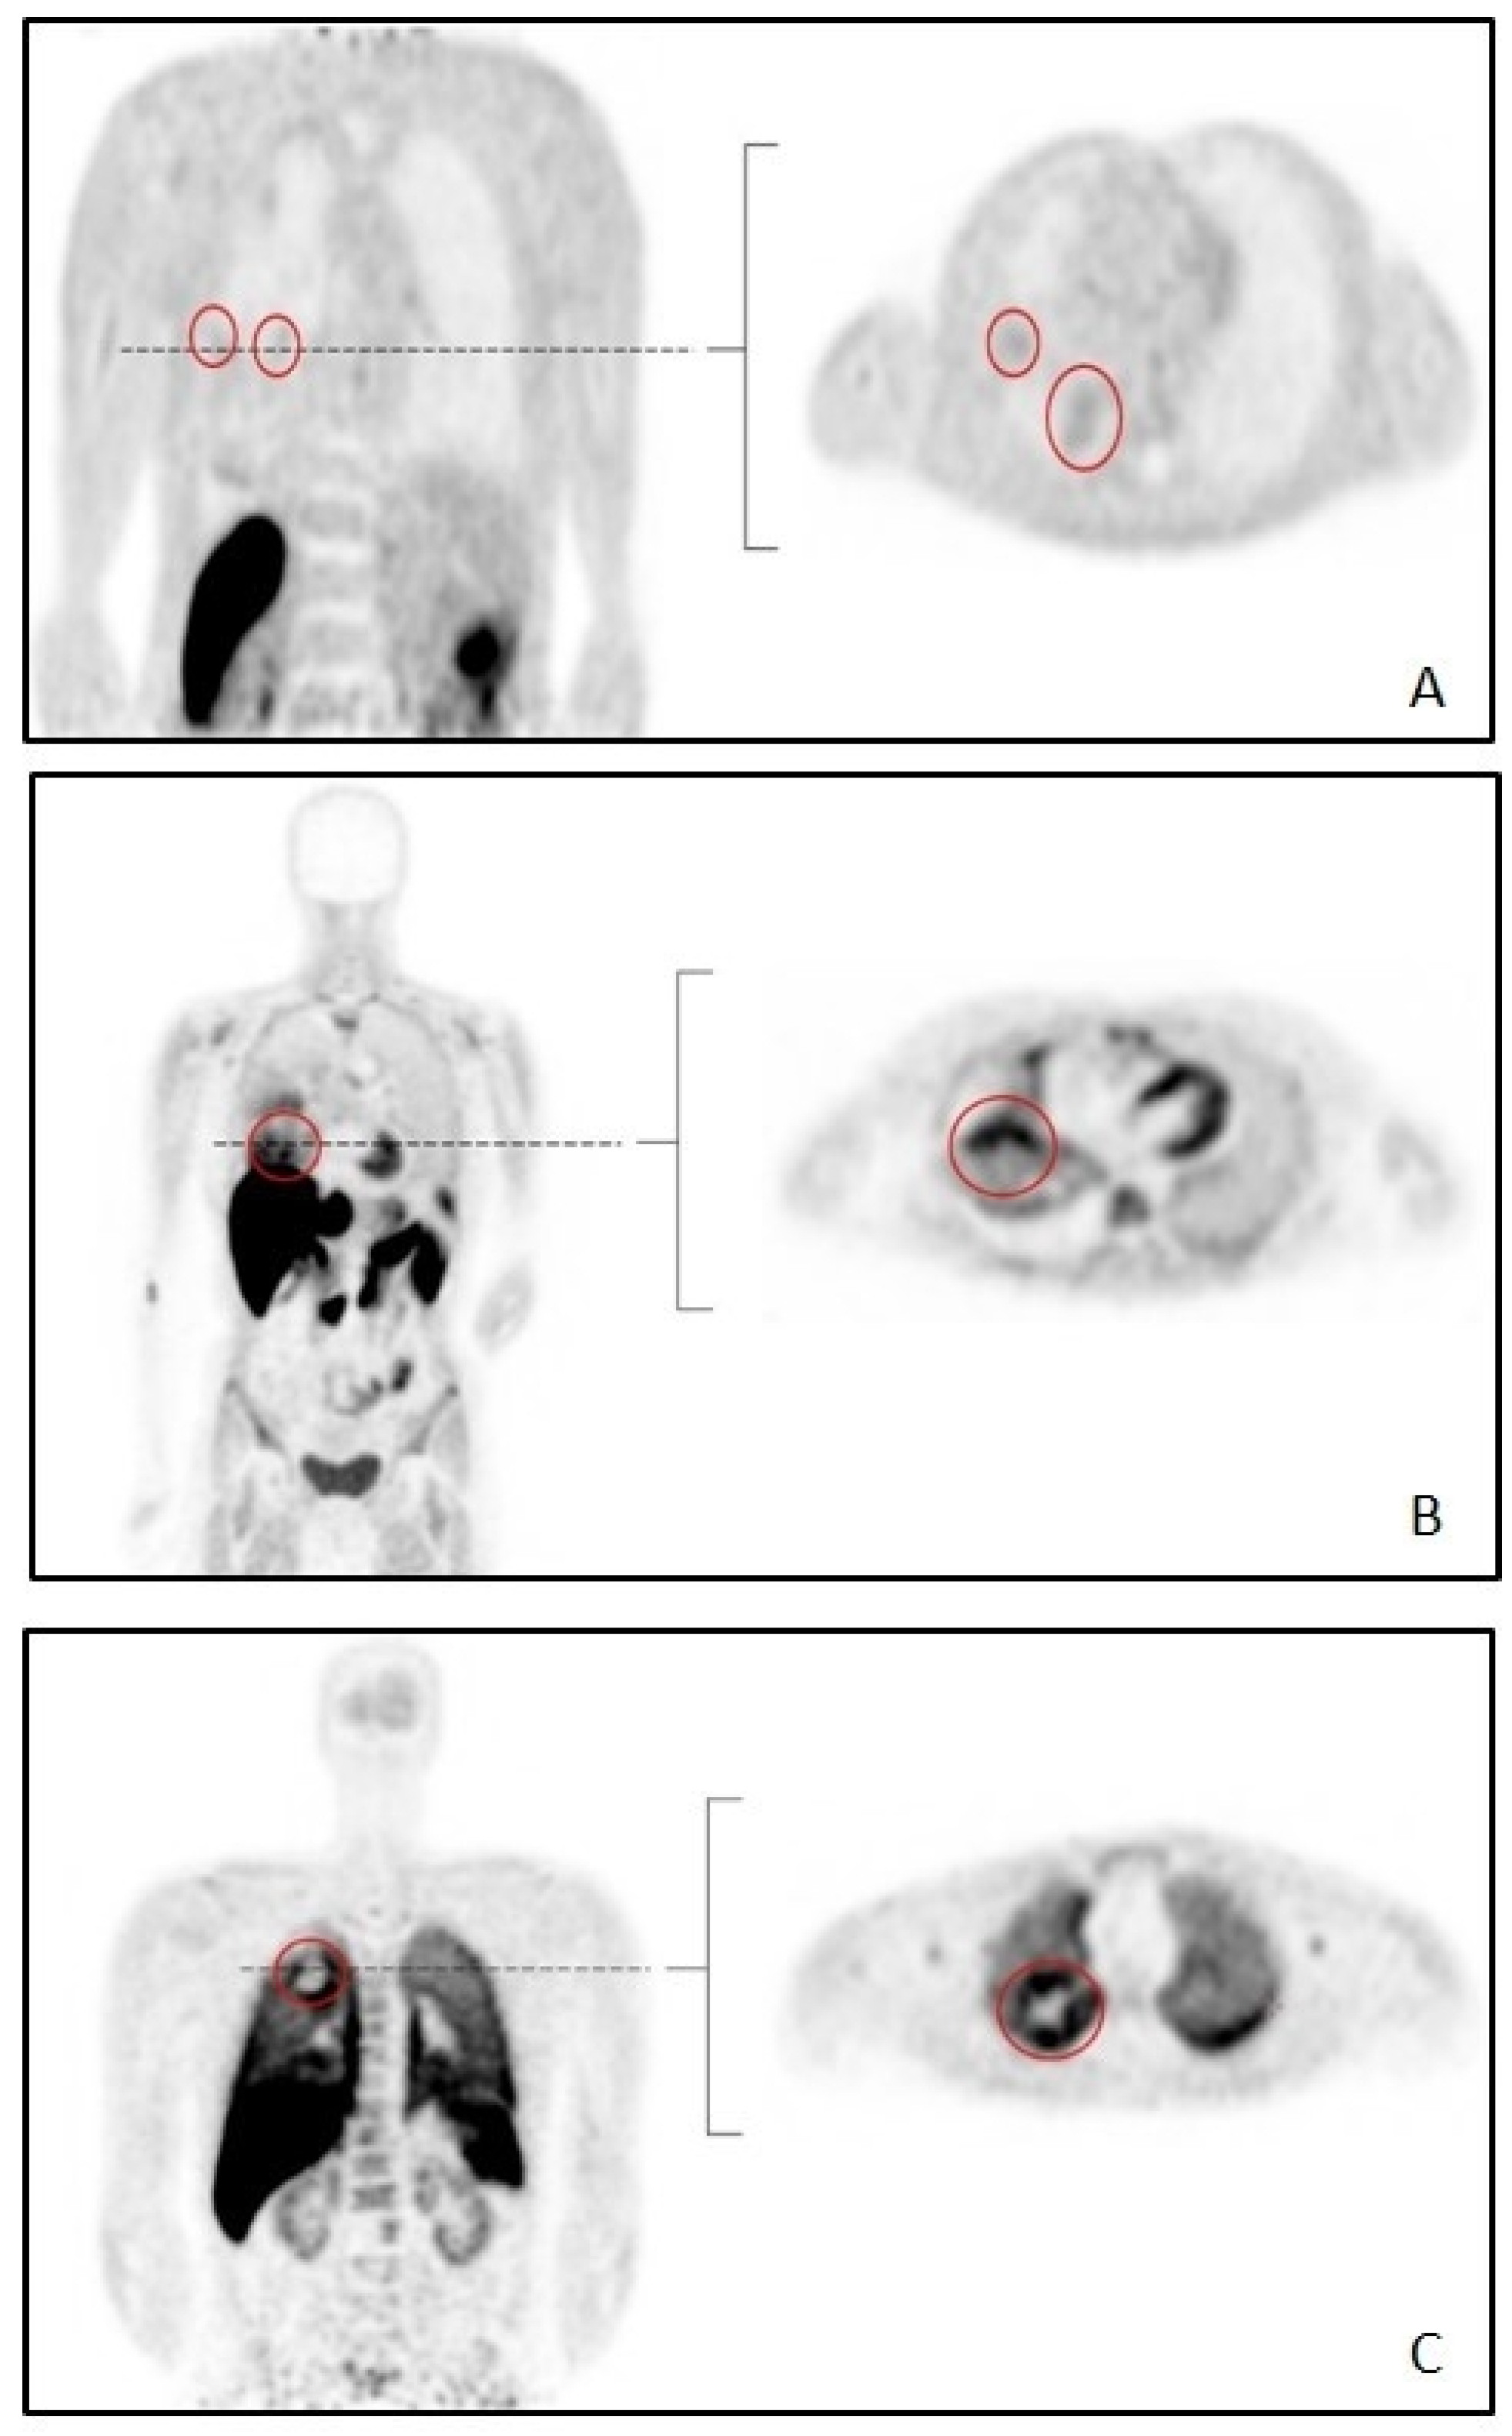

2. Methods

3.4. Static SUV and TBR Analysis

3.5. Tumor-to-Lung Contrast and Noise